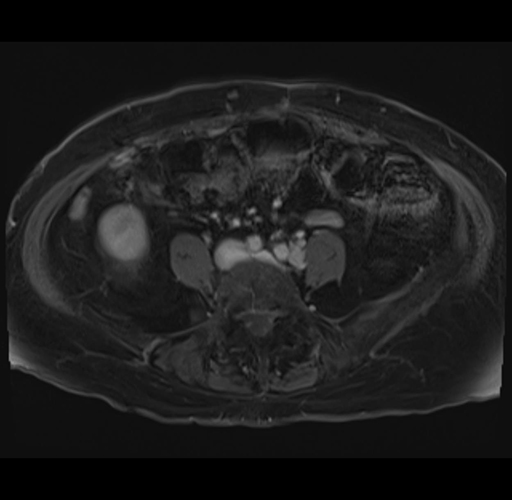

MRI T1

Imaging analysis

Based on your CT findings, which issue(s) would give reason for "planned slowing down moment(s)" in this case?

Considering a standard right hepatectomy procedure, what step(s) of the operation would you do differently in this case?